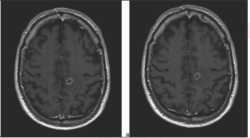

Similarly, MR imaging can also be used for grading neurological tumors. Another study conducted by Bai et al., utilized radiomic data, such as the water molecular diffusion heterogeneity index (WMDHI) and the mean kurtosis values for predicting the grade of gliomas. The study concluded that both of these metrics were higher in high-grade gliomas when compared to low-grade gliomas (P<.05). With the same metrics, the researchers determined specific cut-off values for differentiating high-grade gliomas from low-grade gliomas. After cross-referencing with subsequent surgical biopsies, the sensitivity of both the metrics was 92.9 percent, with specificity being 100 percent, demonstrating itself as a precise model(9).

Virtual biopsy can not only aid in diagnosis of tumors, but it can also use radiogenomic data to go a step further to help plan the treatments, as well. For example, one study examined its application in treatment planning for patients with glioblastoma. Previous research established that the isocitrate dehydrogenase mutation in glioblastoma is associated with a slower progression rate.

Patients affected with glioblastoma tumors that carry this mutation have completely different treatment options in terms of urgency of surgical intervention and adjuvant therapy. In a study conducted by Arnout et al., through MR imaging and radiogenomics, his team was able to correctly identify IDH status in three different cohorts at an 87 percent-to-89 percent accuracy when confirmed by subsequent brain biopsies(11).